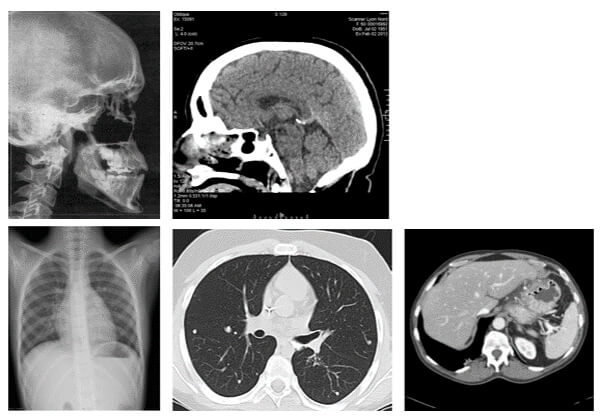

2 Dimensions

These images show us axial and coronal images in a 2D scanning mode.

3 Dimensions

The image on the right side shows the Circle of Willis and the Superior sagittal sinus reconstructed using a volume rendering technique.